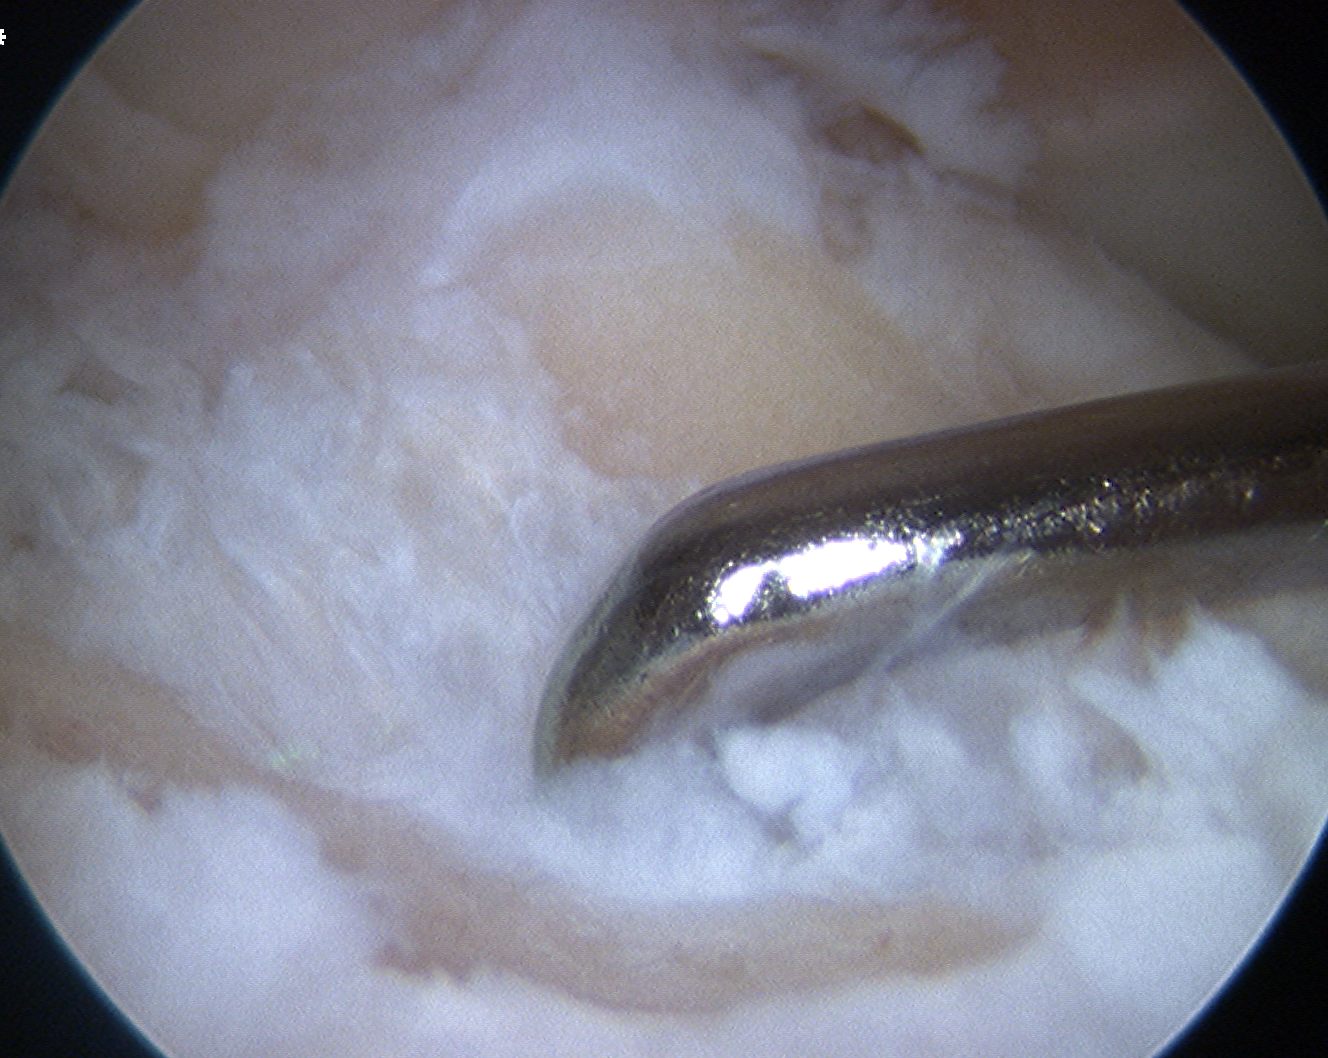

Achilles allograft used, and 12 mm x 20 mm bone plug used in femoral side. Both tunnels drilled where indicated.

Tibial screw ignored, old femoral tunnel ignored. 12 mm tunnels drilled.

Old staple had to be removed. Graft passed and fixed on femoral side with 9 x 25 mm screw.